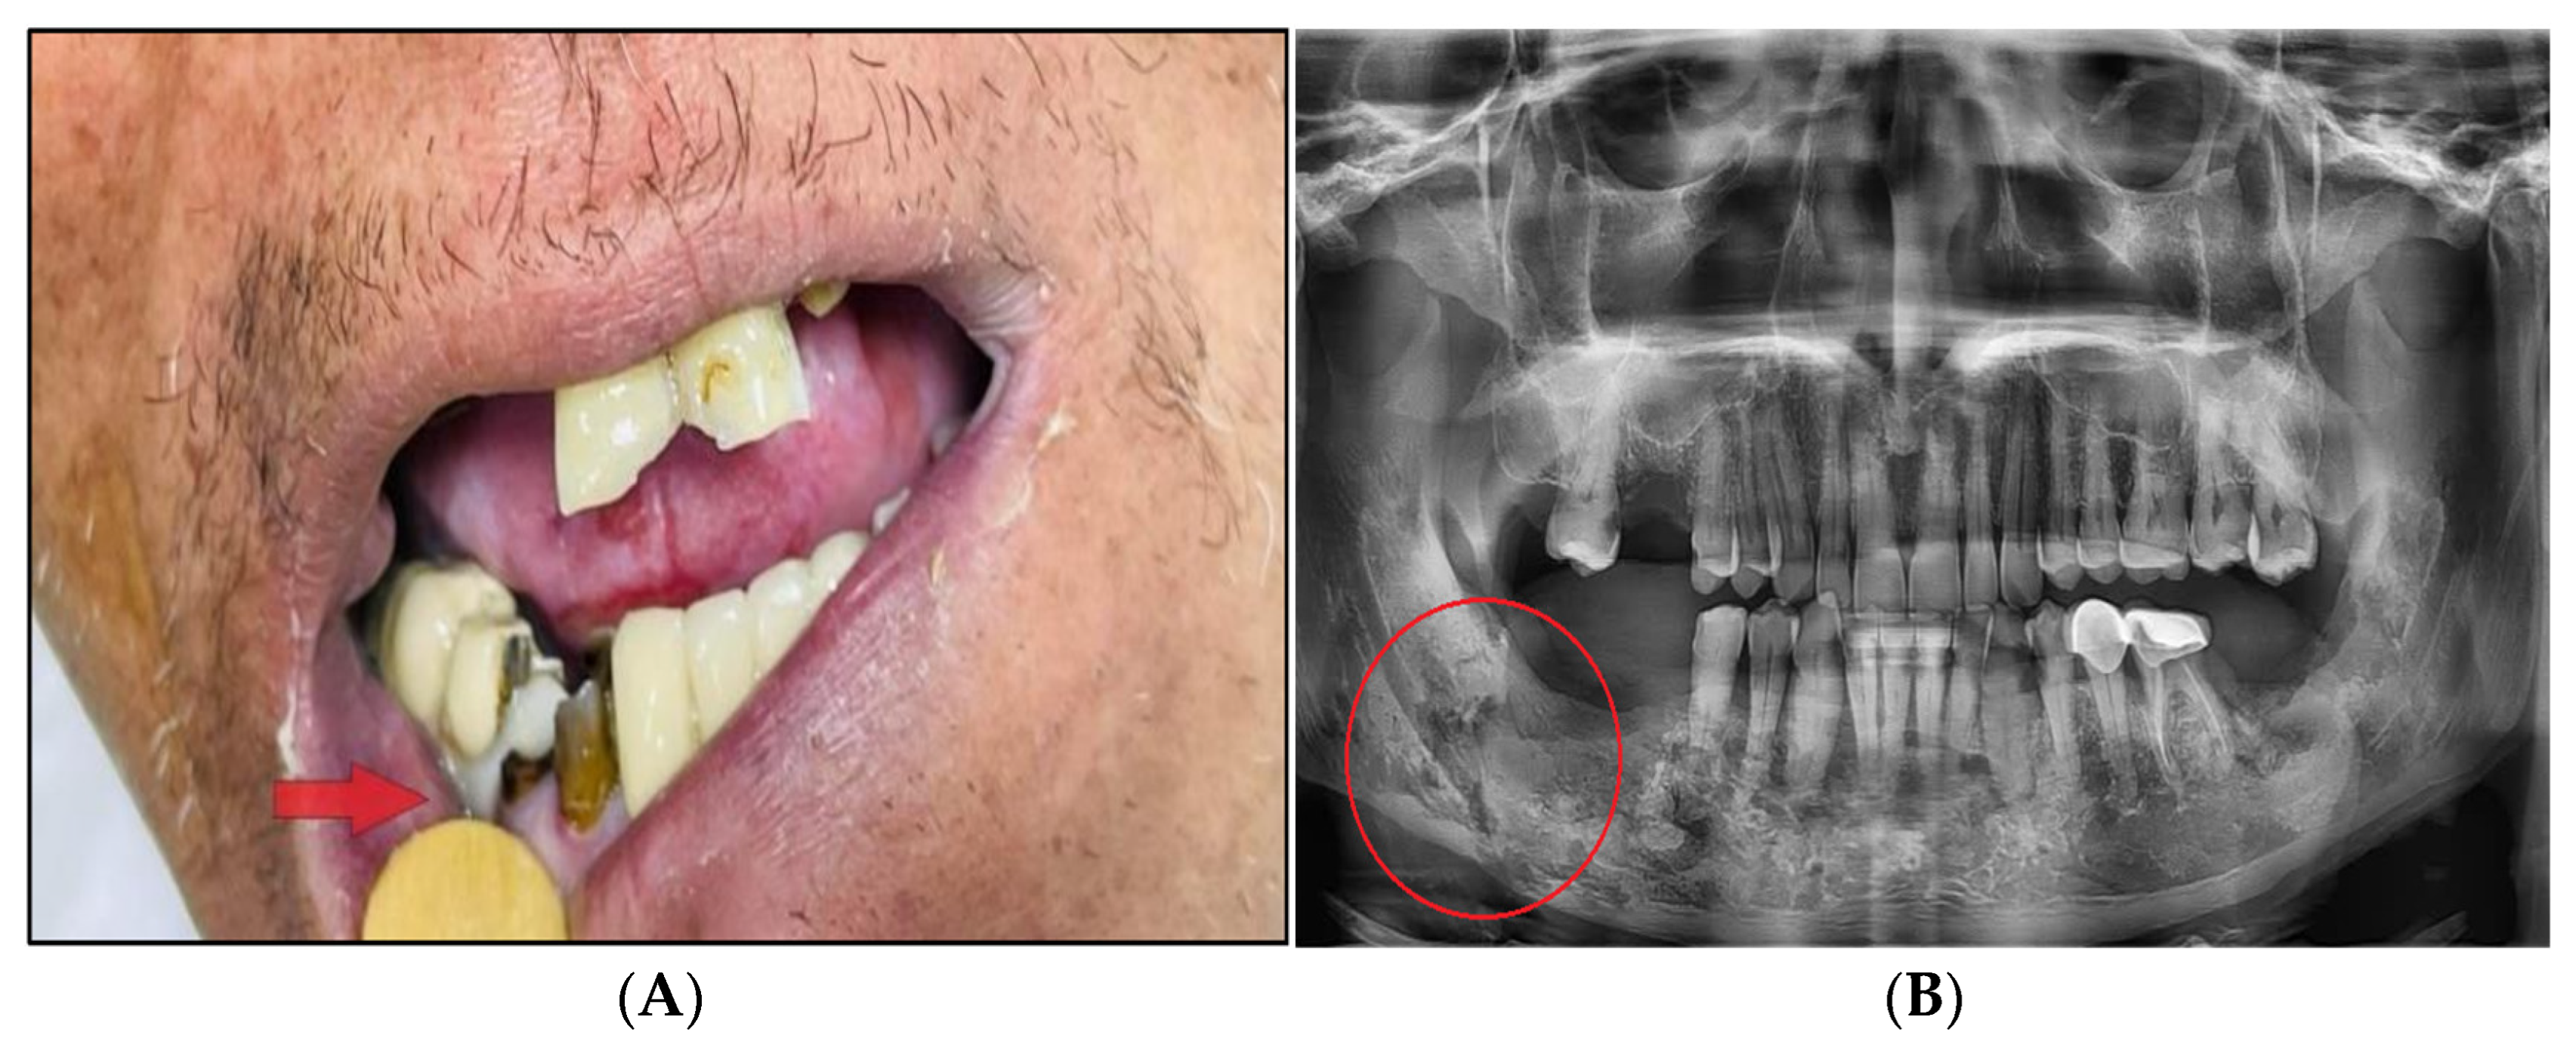

Osteoradionecrosis (ORN) refers to ischemic bone necrosis that is not healing due to RT exposure (Figure 7). It is characterised by soft tissue necrosis and may last three months [7,42]. The history of ORN goes back 100 years to when it was first noted in 1922 by Regaud. ORN is uncommon (5–15% only) but can have a significant negative influence on QoL [65,66]. Modern RT techniques can lower the ORN risk of occurrence. In this review, ORN prevalence was 7.4% with conventional RT, 6.8% with chemoradiation, 5.3% with brachytherapy, and 5.1% with IMRT [9]. A newer study showed the lowest incidence of ORN with proton RT compared to IMRT, 2% vs. 7.7%, respectively [67]. In addition to the selective suppression of osteoclasts in radiated bone, the pathophysiology of ORN is attributed to the concept of “three-H-H-H” (hypocellularity, hypervascularity, hypoxia) of bone that is caused by RT [68]. Subsequent trauma (primarily dental extraction) or spontaneous disruption of the oral mucosa will then be associated with a significant amount of bone fibrosis and damage to the remodeling system (osteocytes, osteoblasts, and osteoclasts) [69]. These alterations eventually result in a non-healing process that can lead to necrosis with or without infection [8,11,68].

Figure 7.

After receiving radiation therapy, a male patient with HNC developed osteoradionecrosis, which is defined as bone necrosis combined with soft tissue necrosis (A) and osteoradionecrosis on an X-ray (B).